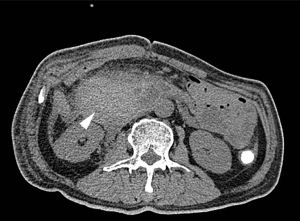

A plain computed tomography (CT) scan showed marked enlargement of the gallbladder with multiple stones in the lumen (Figure 1A). The gallbladder wall measured approximately 2.4 mm in thickness. From clinical manifestations and imaging profiles, the diagnosis was clearly acute calculus cholecystitis. For such cases, emergent or early LC (usually within 1 week from onset) is recommended to ensure a favorable outcome for most patients (1).

Twenty-five days after PTGBD, the patient returned to our emergency department for sudden epigastric pain and worsening vomiting of stomach contents over the previous 48 hours. Due to puncture site pain upon activity, the patient maintained reduced physical activity predominantly by bed rest, maintained low-fat diet without specific dietary modifications, and consistently adhered to dual antiplatelet therapy. Laboratory findings were as follows: WBC 12.98×109/L; hemoglobin level, 87 g/L; platelet level 265×109/L; PT, 15.9 s; PT-INR, 1.52; blood amylase level, 58 U/L; alanine transaminase (ALT) level, 178 U/L; aspartate transaminase (AST) level, 60 U/L; gamma-glutamyl transferase (GGT) level, 288 U/L; alkaline phosphatase (AKP) level, 270 U/L; total bilirubin, 23.1 mmol/L; and albumin, 33.7 g/L. Upper gastrointestinal tract radiography (Figure 1B) showed gastric outlet obstruction, which was further confirmed to be a confined mass located at the second part of the duodenum by CT (Figure 1C).

From a CT scan of the upper gastrointestinal tract, the initial diagnosis made was acute gastric outlet obstruction and mass (undefined) of the duodenum. To clarify the source of the duodenal mass, the patient was sent for endoscopic ultrasonography (Figure 1D), which revealed a compressing mass about 6 cm outside the duodenal cavity which was highly suspected to be an intramural duodenal hematoma (IDH).

Cholangiography via PTGBD was performed to help identify the bleeding source and detect any biliary tract variations (which could facilitate avoiding bile duct injury during elective LC; Figure 1E) (6). The cholangiography unexpectedly revealed an internal fistula between the gallbladder and IDH, which was subsequently confirmed by CT scan with the appearance of medium contrast in the IDH (Figure 1F).